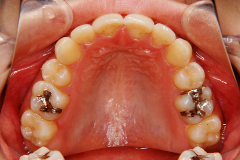

口腔内写真,レントゲン

(必要に応じてCT)

ステップ3. レントゲン(パノラマ、セファロ)撮影・口腔内写真撮影

口腔内写真、レントゲン(必要に応じて CT )、印象(歯型)採得